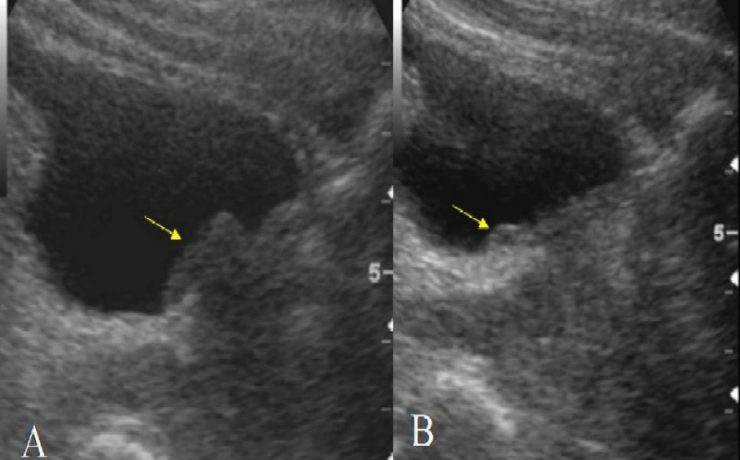

Revista Anales de Radiología de México. Ultrasonido Tiroideo en pacientes dediatricos del HIM, con diagnostico clínico de Tiroiditis de Hashimoto. México 2012 (11) – 1. Se revisaron 64 pacientes, por US más frecuente en mueres 9/1, y la lesión común es nódulo único, hipoecogénico, con contenido sólido, con vascularidad periférica.